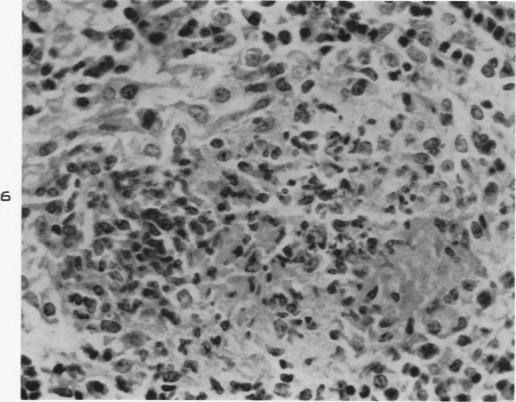

Experimental moniliasis in mice.

Am J Pathol. 1955 Sep-Oct;31(5):859-73.